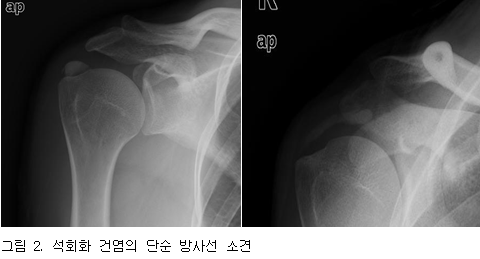

출처: 대한류마티스학회

출처: 대한류마티스학회 석회화 건염은 앞에서 설명한 특징적인 급성 통증 증상 및

영상검사(방사선, 초음파, MRI)를 토대로 진단합니다.

엑스레이 촬영으로 하얗게 침착된 석회를 발견할 수 있습니다.

뼈가 석회를 가리는 위치에 있으면 석회를 찾을 수 없으나,엑스레이 촬영시 다각도로 촬영을 하면

숨어 있는 석회를 대개 찾을 수 있습니다.

대부분 타원형의 형태를 보이지만

경우에 따라서는 부정형인 경우도 있으며,

매우 작은 경우에는 점처럼 나타나기도 합니다.